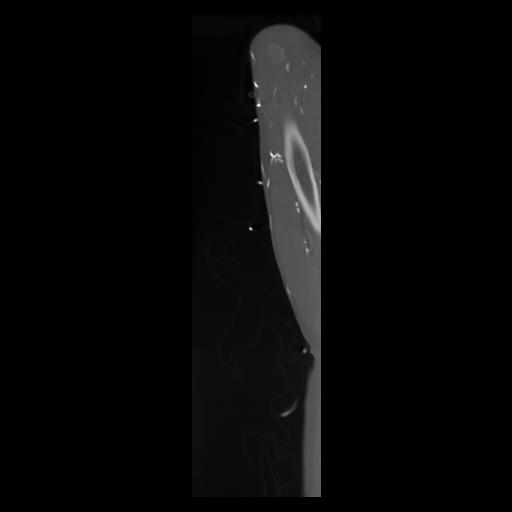

30 CUERPO,CE,Sagittal,3.000,CUERPO,Sagittal,